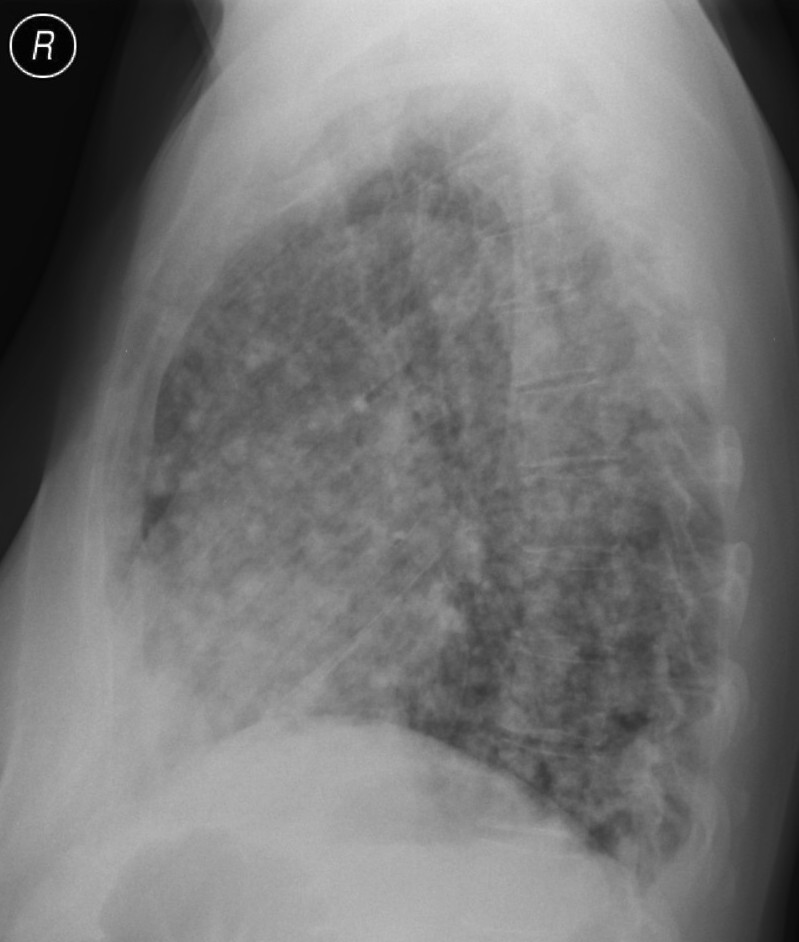

Unklare verdichtungen der lunge links. CAS Article PubMed Google Scholar. Die konventionelle Röntgenaufnahme der Lunge zeigte bipulmonale laterale Verschattungen verdächtig auf das Vorliegen einer atypischen Pneumonie Abb1. Neben der Lungenfunktionsprüfung werden zur Diagnose einer Lungenfibrose bildgebende Verfahren angewandt.

Verdacht auf Erkrankungen der Bronchien der Lunge der Pleura der Thoraxwand des Atemantriebs und der Atemmuskulatur. Neben der Lungenfunktionsprüfung werden zur Diagnose einer Lungenfibrose bildgebende Verfahren angewandt. Krankheiten die sich in den Alveolen dem terminalen Luftraum der Lunge abspielen haben ein anderes radiologisches Bild als solche die im Interstitium der Lunge lokalisiert sind. Verdichtung Röntgen Lunge. Die betroffenen Bereiche der Lunge sehen dann auf den CT-Bildern heller aus als das gesunde Lungengewebe. Wenn die hellen Stellen in der Lunge die Form eines Streifens haben dann sagt der Arzt dazu streifige Verdichtung. Es wird meist in der Neonatalperiode diagnostiziert und manifestiert sich klinisch in einer unterschiedlich ausgeprägten Tachypnoe. Die optimale Perfusions- und Ventilationsverteilung an dieser komplexen Oberflächenstruktur ist Voraussetzung für deren Diffusionseigenschaften Abb. Schranz Kinderherzzentrum der Universität Gießen danken.

Daher ist die linke Lunge viel kleiner als die rechte Lunge das Herz nimmt den Raum auf der linken Seite ein. Störungen des Gasaustausches. Bei manchen Erkrankungen oder Veränderungen lässt die Lunge die Röntgenstrahlung weniger gut durch als normal. Pneumologische Leitsymptome Atemnot Husten Auswurf. Außerdem liefert sie die Basis für die Entscheidung zu bildgebenden Verlaufsbeobachtungen. Nun habe ich unheimliche Angst das sich der Verdacht bestätigt. Dieser medizinische Begriff wurde für Sie übersetzt von.